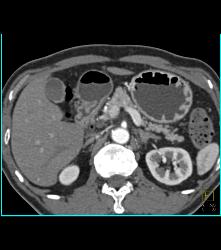

Antral Carcinoma With Adenopathy